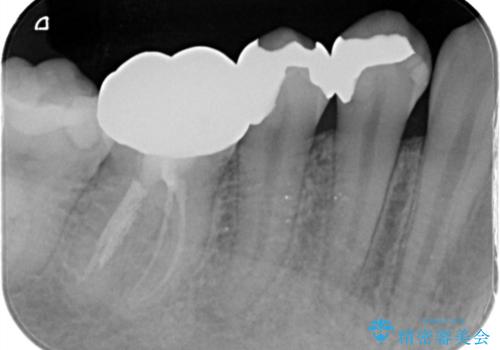

- 右下が痛くて噛めないとの理由で来院された患者様です。レントゲン撮影、歯髄の診断等から、根管治療、歯髄保存療法が必要と判断し、治療後に丈夫で審美性に優れたセラミックインレー、フルジルコニアクラウンを被せました。